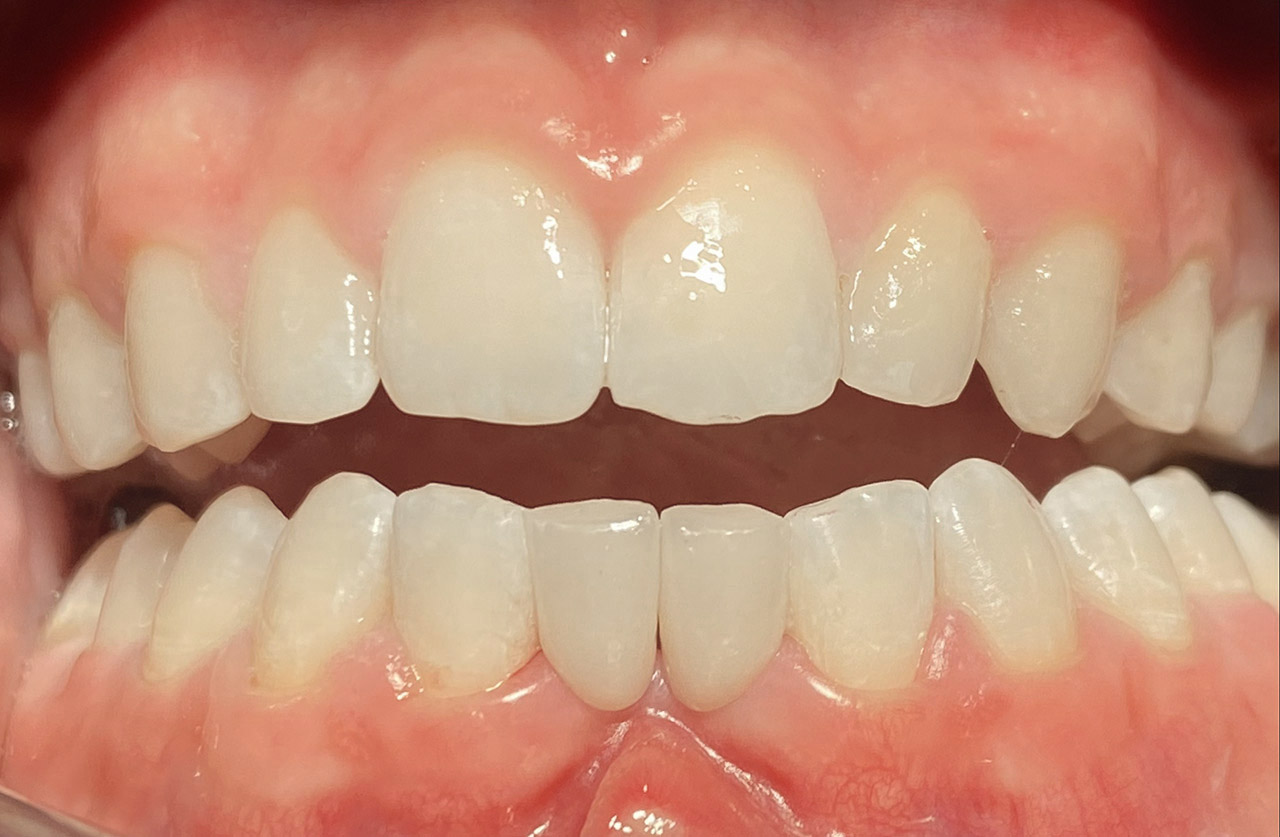

Reinigung der Zähne mit Pulverstrahltechnik minimalinvasiv und zahnschonend und wo noch nötig gezielt mit Ultraschall.

Das Resultat 45 Minuten später.